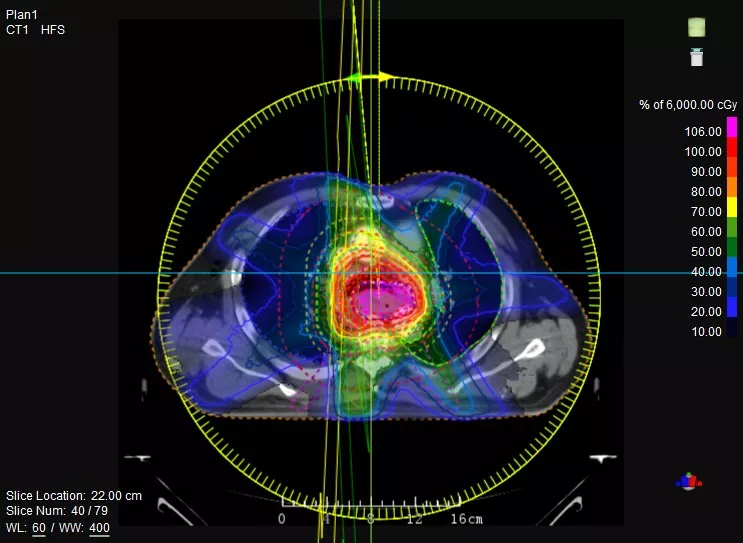

觀其“外在”——首創(chuàng)Linac與CT真正一體化融合,精準(zhǔn)CT模擬定位、高清CT影像引導(dǎo),實現(xiàn)精準(zhǔn)高效的放射治療。

一款設(shè)備即可滿足CT模擬定位、CT影像引導(dǎo)、uARC動態(tài)旋轉(zhuǎn)調(diào)強放療等重要臨床應(yīng)用,無需科室/治療室間切換,一站完成放療全流程。

機(jī)載CT影像可直接用于放療計劃制作

CT-IGRT配準(zhǔn),除骨性標(biāo)記外,還能以器官、軟組織等作為參考,真正找到配準(zhǔn)目標(biāo)

鼻咽癌患者,進(jìn)行旋轉(zhuǎn)容積調(diào)強治療(uARC)